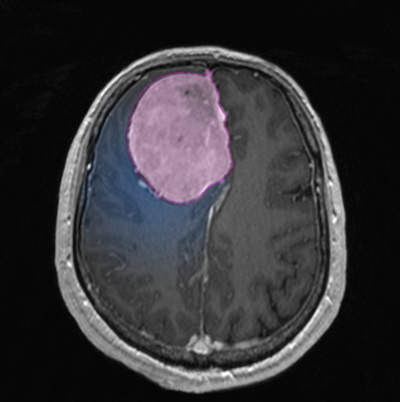

Διάγνωση Απαραίτητα είναι: Η λεπτομερής λήψη ιστορικού και η κλινική εξέταση, Η μαγνητική τομογραφία του εγκεφάλου με σκιαγραφικό, Σε ορισμένες περιπτώσεις: Η μαγνητική αγγειογραφία ή/και φλεβογραφία του εγκεφάλου, Η μαγνητική φασματοσκοπία, Η μαγνητική τομογραφία του εγκεφάλου με σκιαγραφικό για νευροπλοήγηση, Σε περίπτωση εξεργασίας/εξεργασιών με υποψία μεταστατικής προέλευσης επιπλέον ογκολογικός έλεγχος (απεικονίσεις άλλων οργάνων, καρκινικοί δείκτες κα) |